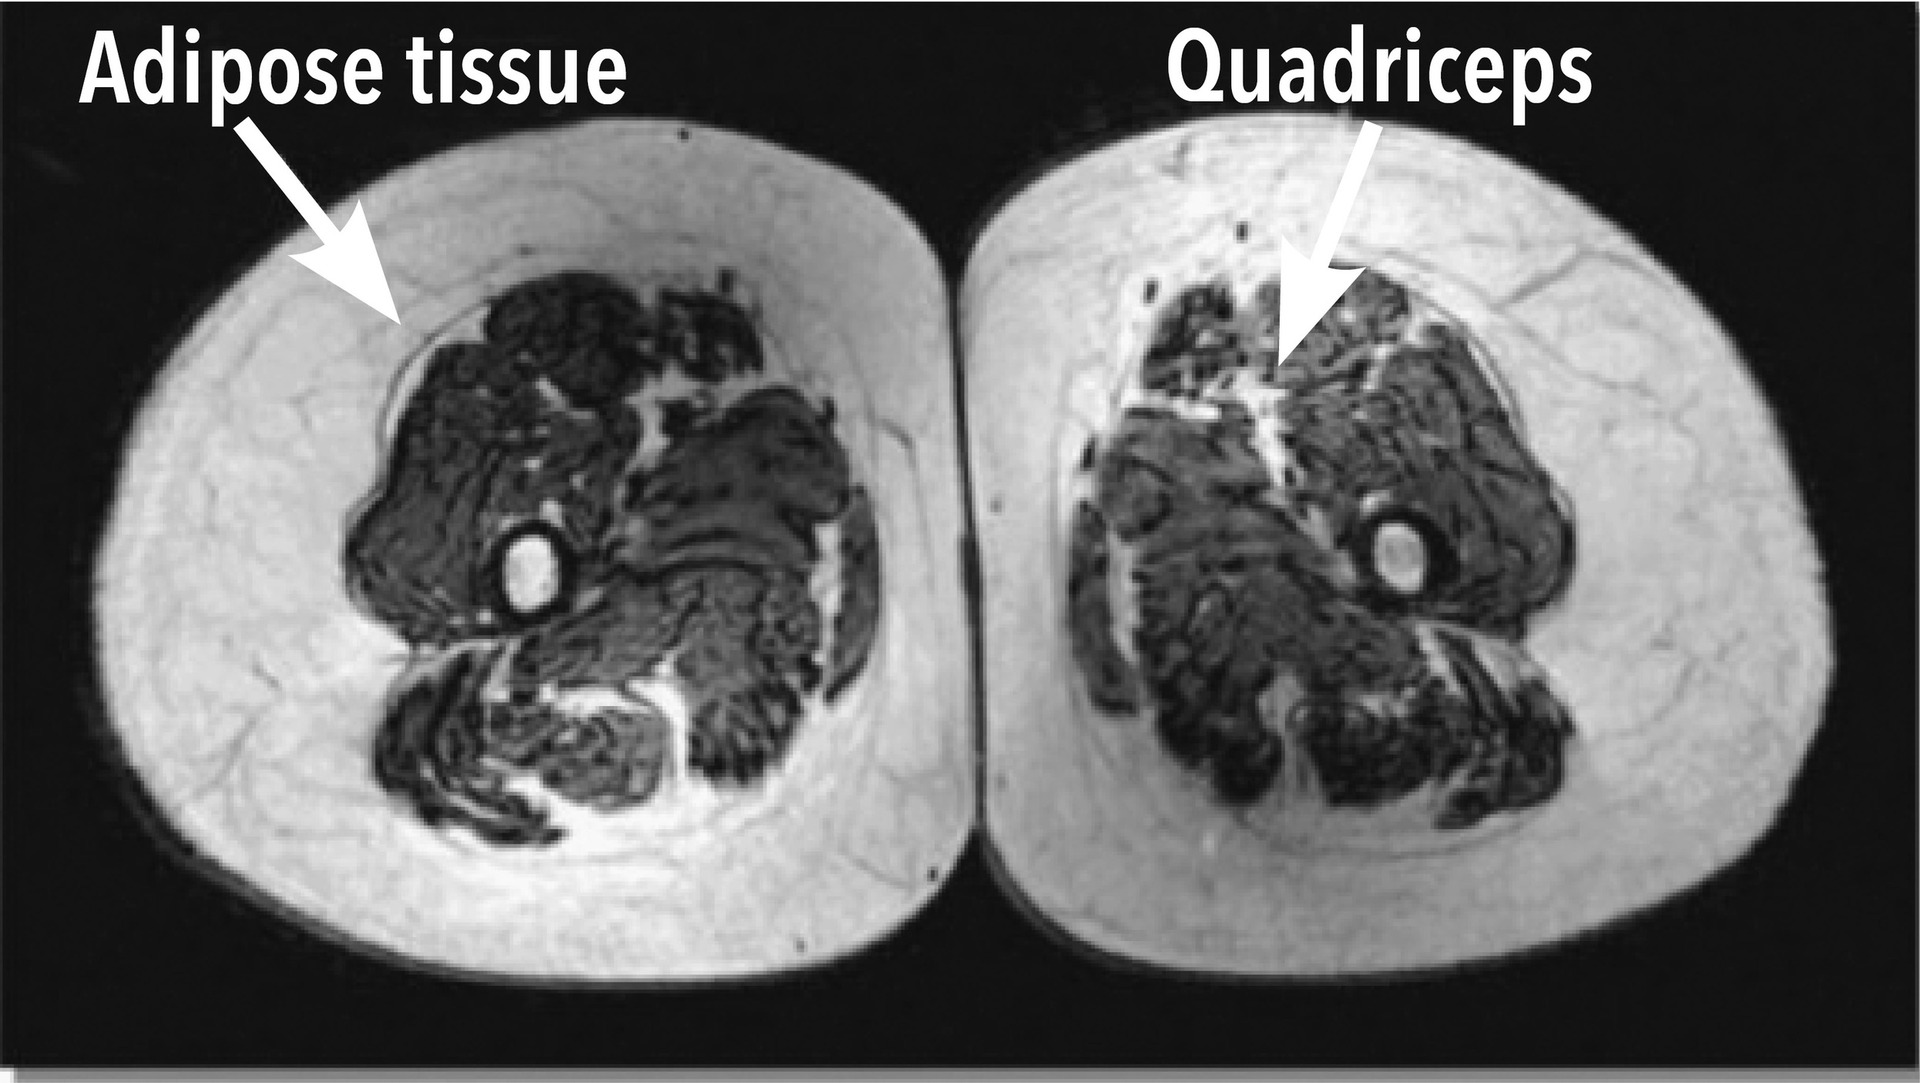

Xin cảm ơn sự đồng ý của tạp chí Physician and Sportsmedicine, Berwyn, PA cho phép tái xuất bản các hình ảnh trên trang này từ bài viết “Tập luyện kéo dài giúp duy trì khối lượng cơ bắp ở các vận động viên lớn tuổi” của tác giả Wroblewski A.P. (đồng tác giả chính), Amati (đồng tác giả chính), Smiley M.A., Goodpaster B., Wright V. từ tạp chí Physician and Sportsmedicine, 2011. Sử dụng với sự cho phép của tạp chí Physician and Sportsmedicine, Berwyn, PA.